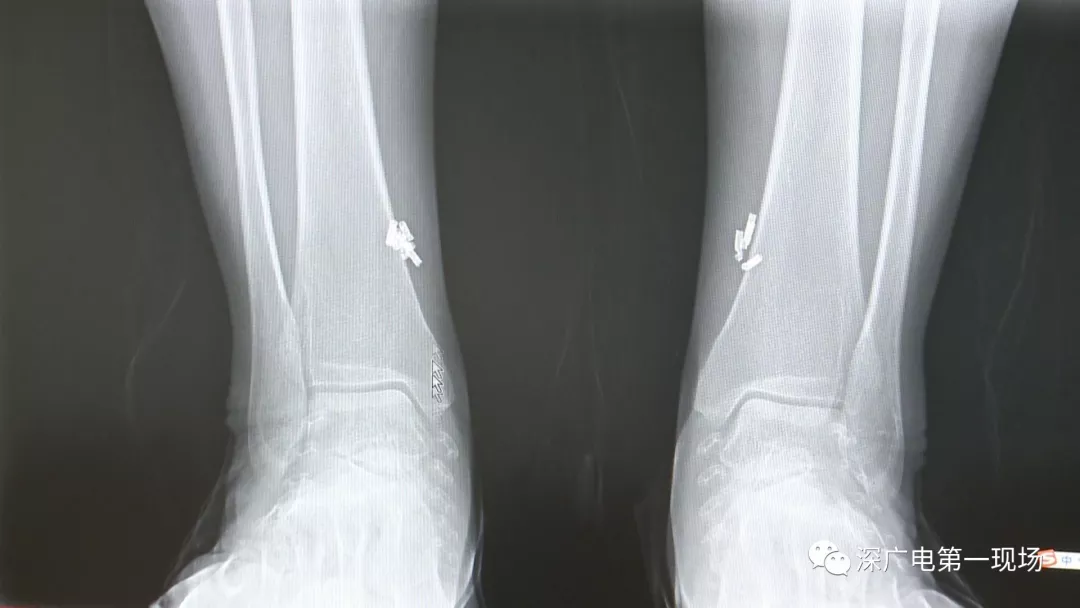

从X光影像图片中可以看到

患者周身布满了弹簧圈

深圳大学总医院神经外科副主任医师陈富勇介绍,当时检查的时候发现,该患者从头部到腿部,基本上每个地方都有弹簧,很难数清具体数目。